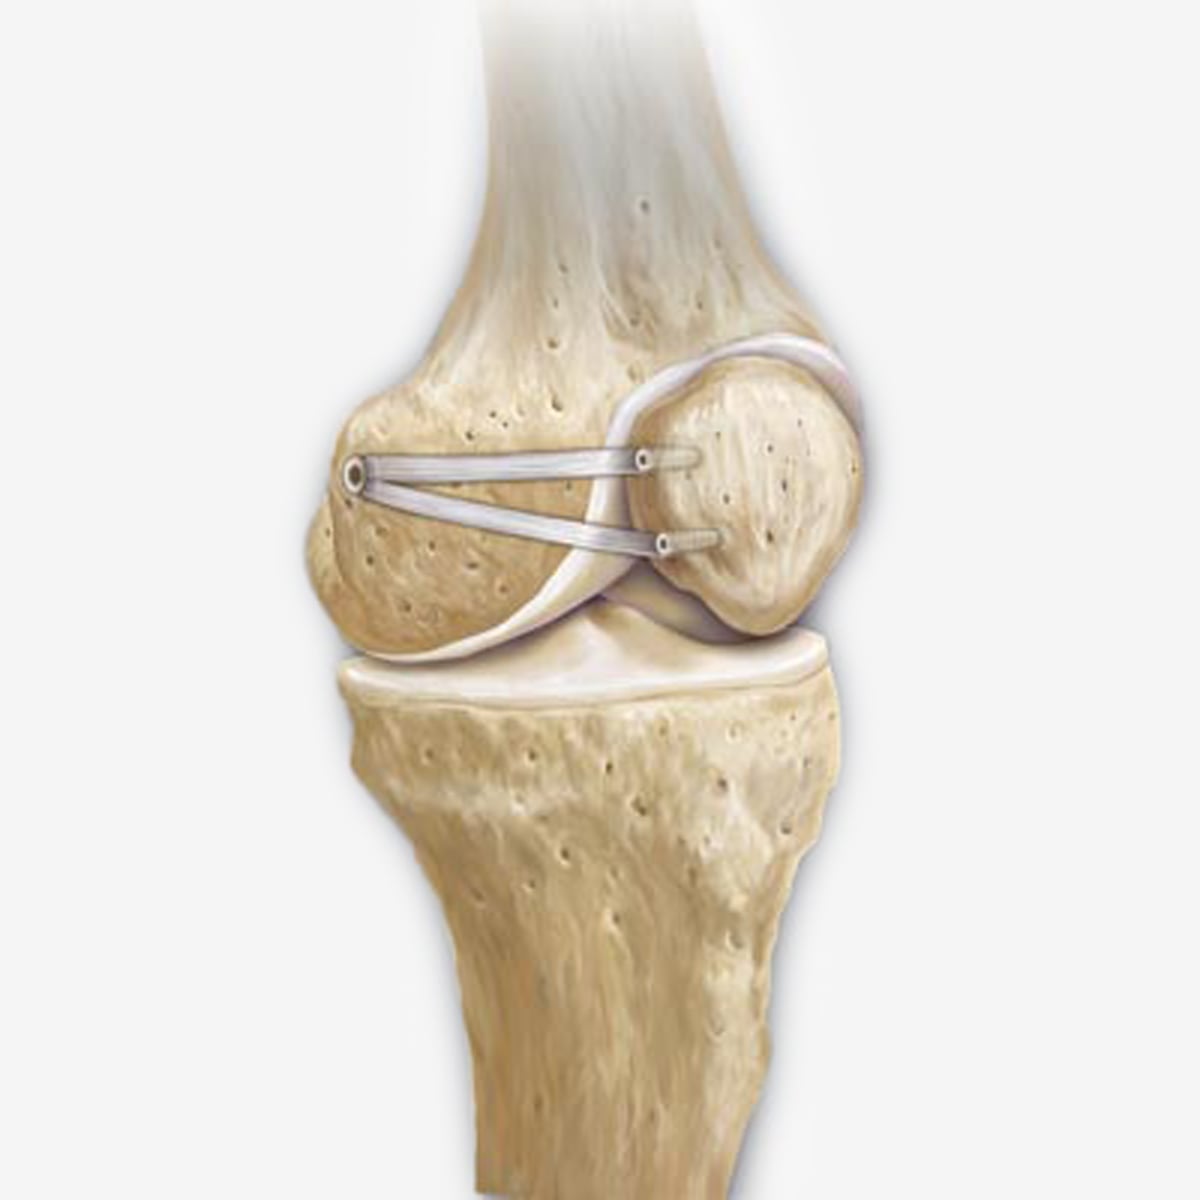

Das Mediale Patellofemorale Ligament, kurz MPFL, ist DER entscheidende passive Stabilisator des patellofemoralen Gelenks (Kniescheibe und Oberschenkelknochen).

Eine unzureichende Funktion des MPFL spielt eine wesentliche Rolle bei der Entstehung der patellofemoralen Instabilität. Es ist von höchster Bedeutung zu verstehen, dass eine Insuffizienz oder das Fehlen der Funktion des MPFL die Grundvoraussetzung für eine patellofemorale Instabilität darstellt. Studien, insbesondere von Prof. Schoettle, haben gezeigt, dass bei über 90% der Patienten mit einer vorherigen Patellaluxation eine gerissene oder unzureichende MPFL vorliegt.

Es ist wichtig, zwischen einer akuten, frischen Ruptur nach einem traumatischen Luxationsereignis und einer chronischen Insuffizienz oder einer Unterentwicklung des MPFL bei Patienten mit langanhaltenden habituellen Patellaluxationen zu unterscheiden. In letzterem Fall können verschiedene prädisponierende Faktoren zugrunde liegen. Die richtige Diagnose und die genaue Lokalisation der MPFL-Ruptur an der Kniescheibe oder dem Oberschenkelknochen sind von entscheidender Bedeutung für die korrekte Behandlung.

Die MPFL-Rekonstruktion kann sowohl allein als auch in Kombination mit anderen Verfahren indiziert sein. Bei einer isolierten Ruptur des MPFL ohne begleitende Pathologien und anhaltende Instabilität sowie Rezidivluxationen kann eine isolierte MPFL-Rekonstruktion in Betracht gezogen werden. Dies ist besonders häufig bei traumatischen Patellaluxationen der Fall, bei denen es durch direktes Anpralltrauma zur Patelladislokation und Ruptur des MPFL ohne Vorliegen prädisponierender Faktoren kommt.

Bei Patienten mit chronischer MPFL-Insuffizienz und nur leichter Trochleadysplasie kann die isolierte Rekonstruktion des MPFL ausreichen, um die Patella ausreichend zu stabilisieren. Dies ist bei den meisten Patienten mit Patellaluxation der Fall. Insgesamt weisen bis zu 96% der Fälle von patellofemoraler Instabilität mehr oder weniger ausgeprägte Formen der Trochleadysplasie auf. Durch die korrekte anatomische Rekonstruktion des MPFL kann die Instabilität im Bereich der gestreckten Kniepositionen behoben werden. Dies wird insbesondere für Patienten mit femoralen MPFL-Abrissen empfohlen.